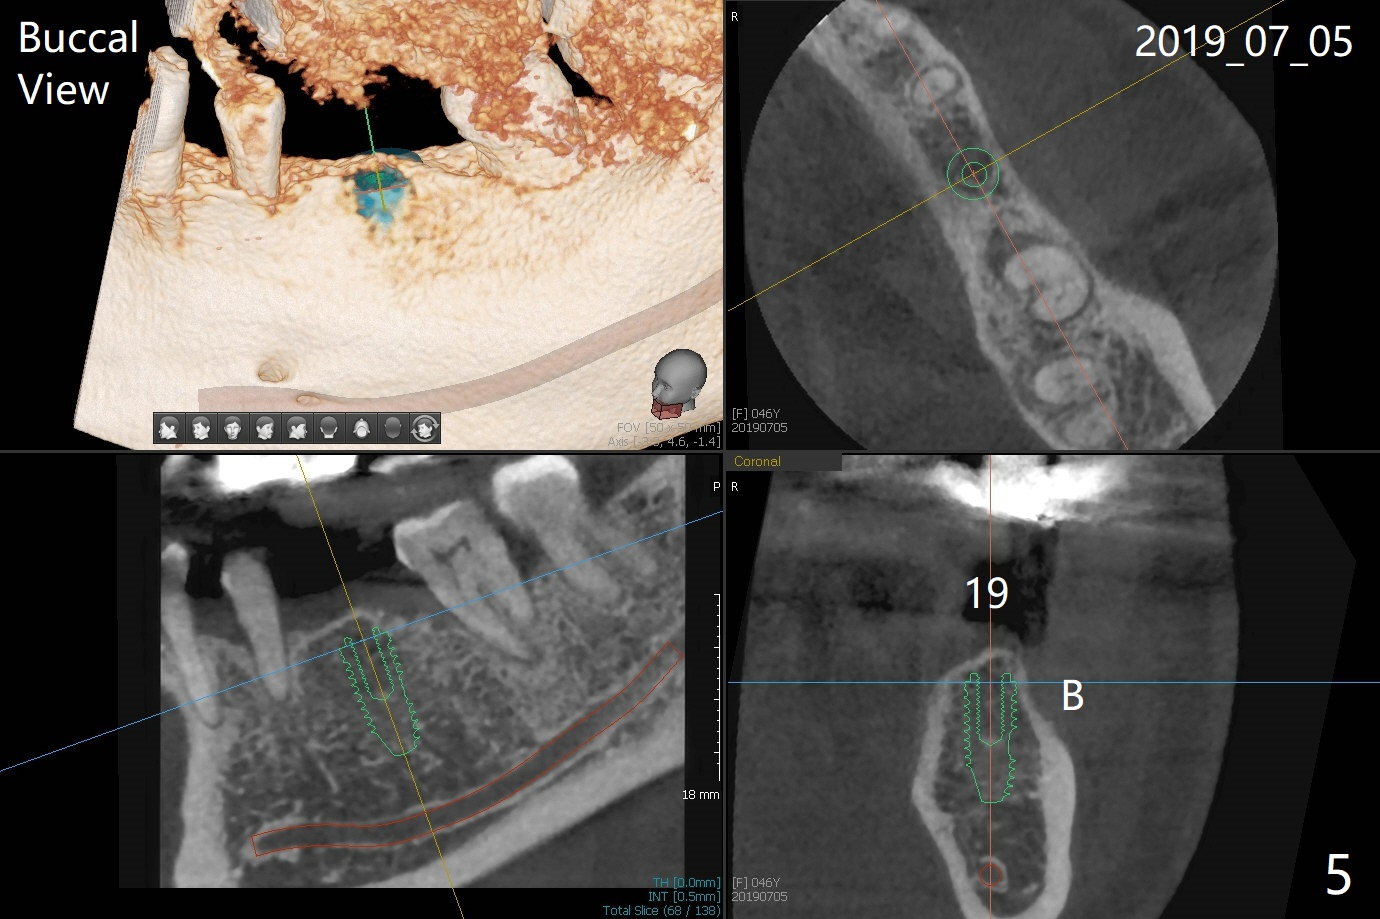

A 46-year-old woman had severe periodontal abscess lingual to #18-20 FPD a year ago (Fig.1,2 *). After SRP and Arestin placement #18 ML, the FPD was sectioned (Fig.2 >) to determine which abutment is to be extracted for implant. Since the sectioning, the patient has been unable to masticate on the left side (Fig.3). With removal of the FPD, CT is taken for surgical guide. Are the abutments salvageable (Fig.4,6)?